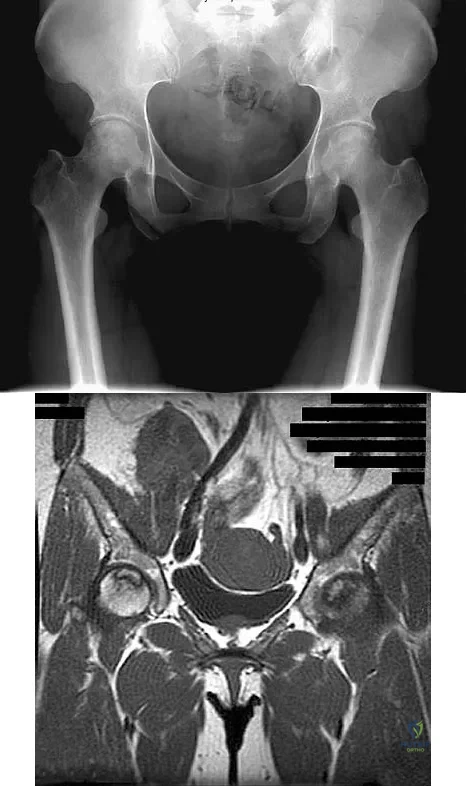

A 46-year-old woman has bilateral groin pain, with more severe pain on the left side than on the right side. Figures 44a and 44b show a radiograph and a T1-weighted MRI scan. What is the most likely diagnosis?

Explanation